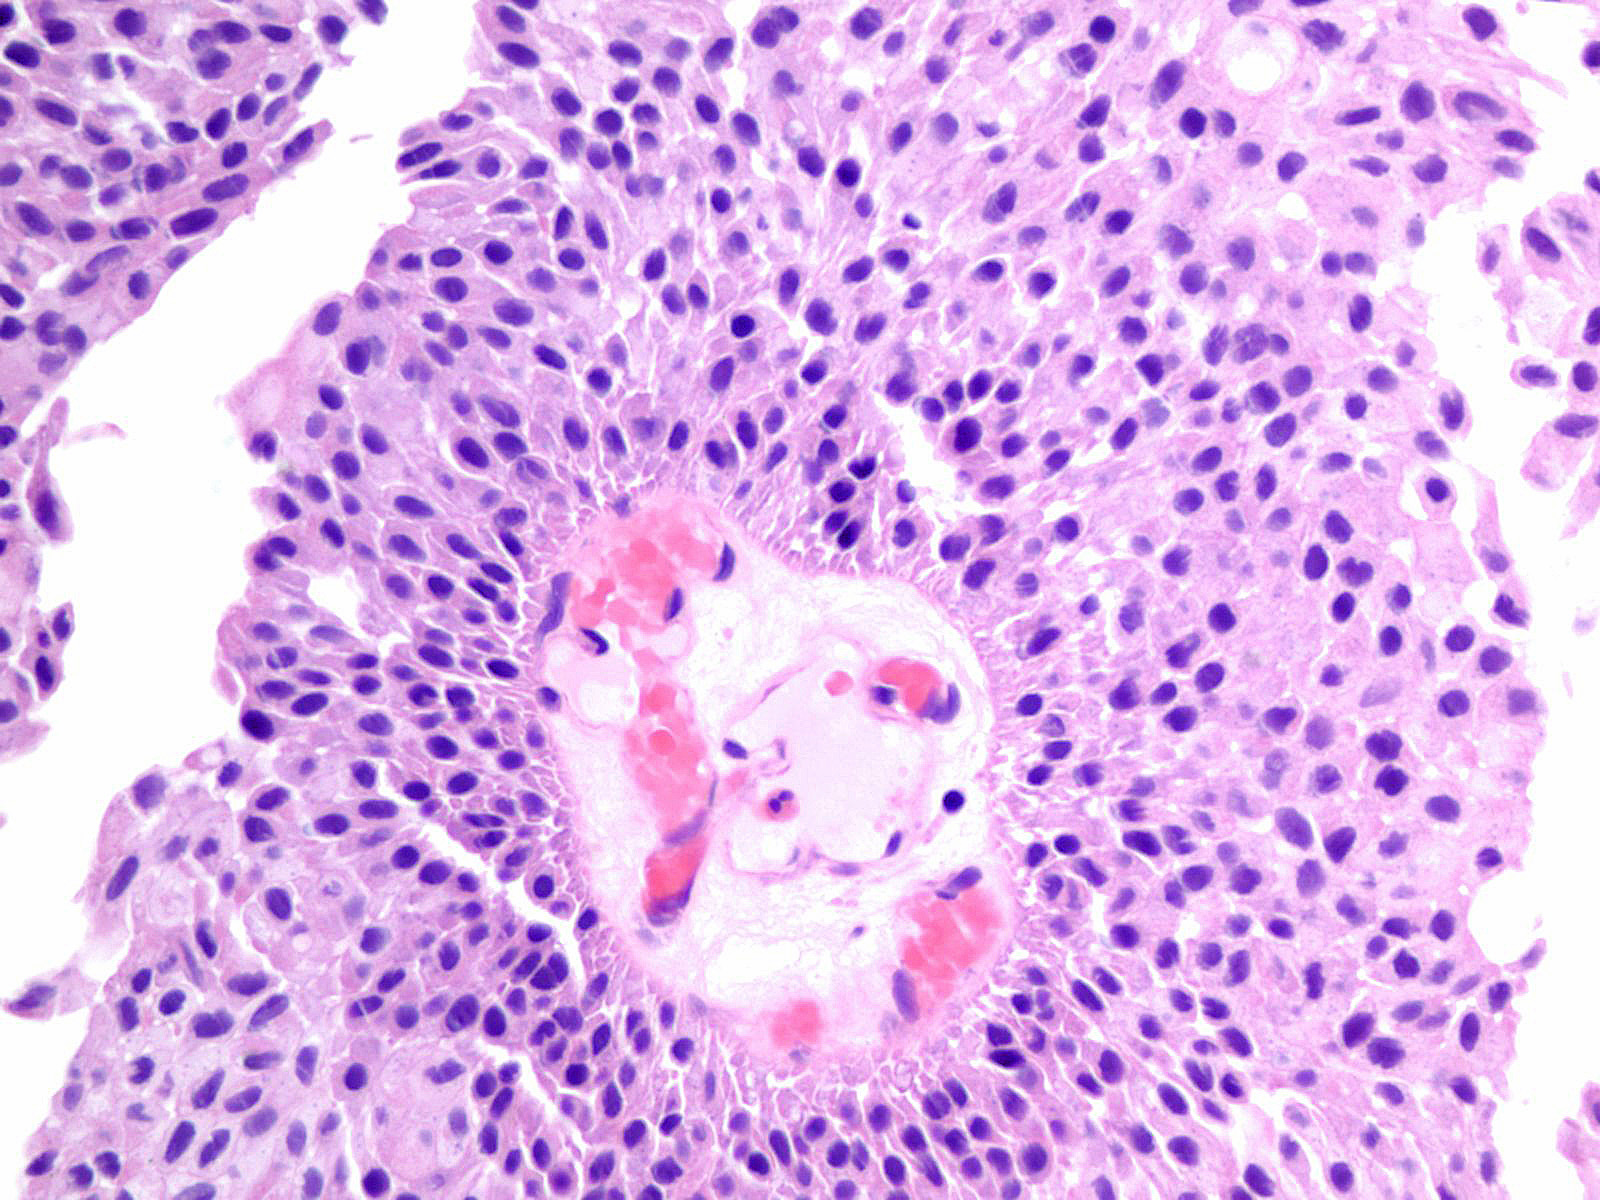

Consensus grade: Low-grade papillary urothelial carcinoma (LG-PUC)

Lesion shows moderate variation in nuclear size, shape and chromatin. Scattered nuclei are significantly enlarged and hyperchromatic relative to other nuclei. Lesion still maintains an overall orderly appearance.